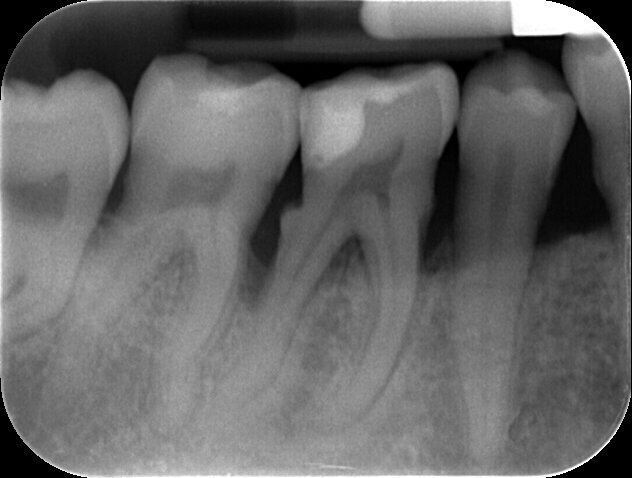

Fig. 3 - Status radiografico al T0.

Fig. 5 - Rx peri-apicale dell’elemento 4.6: difetto intra-osseo e abbondante presenza di tartaro.

A 3 mesi dell’intervento il sito viene valutato nuovamente attraverso ispezione clinica e indagine radiologica; i tessuti molli risultano sani all’aspetto e al sondaggio (assenza di SOP e BOP, sondaggi MV dell’elemento 4.7 e DV dell’elemento 4.6 rispettivamente di 3 e 4 mm) ed i tessuti duri appaiono re-mineralizzati in radiografia, con il difetto intra-osseo completamente ricostruito. Distalmente all’elemento 4.6 si osservi come la papilla interdentale si sia invaginata durante il periodo intercorso tra la rimozione sutura e il controllo a 3 mesi, ciò è dovuto all’utilizzo da parte della paziente di uno scovolino di dimensioni non adeguate che viene prontamente sostituito. Anche dopo la chirurgia, la paziente rimane un soggetto con Periodontal Risk Assessment alto, a causa della perdita ossea e di elementi dentari rapportata con l’età, pertanto si inserisce in un programma di richiami trimestrali di igiene orale professionale in modo da ridurre al minimo il rischio di recidive.

Fig. 15 - Rx peri-apicale dell’elemento 4.6.: re-mineralizzazione dei tessuti duri.